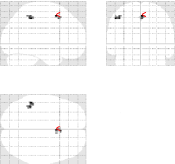

3.2.5 Group-level analysis

Due to between-subject anatomical and functional variability, group-level analysis is necessary in order to derive robust and reproducible conclusions at the population level. For this validation, random effect analyses (RFX) involving fifteen healthy subjects have been conducted on the contrast maps we previously investigated at the subject level. More precisely, one-sample Student’s test was performed on the subject-level contrast images (eg, Lc-Rc, aC-aS,… images) using SPM5.

| mSENSE | UWR-SENSE | 4D-UWR-SENSE | |

|---|---|---|---|

|

|

|

|

|

|

|

For the aC-aS contrast, Maximum Intensity Projection (MIP) Student’s -maps are shown in Fig. 11. First, they illustrate that irrespective of the reconstruction method larger and more significant activations are found on datasets acquired with providing the better SNR. Second, for , visual inspection of Fig. 11 [top] confirms that only the 4D-UWR-SENSE algorithm allows us to retrieve significant bilateral activations in the parietal cortices (see axial MIP slices) in addition to larger cluster extent and a gain in significance level for the stable clusters across the different reconstructors. Similar conclusions can be drawn when looking at Fig. 11 [bottom] for . Complementary results are available in Tab. 5 for and .